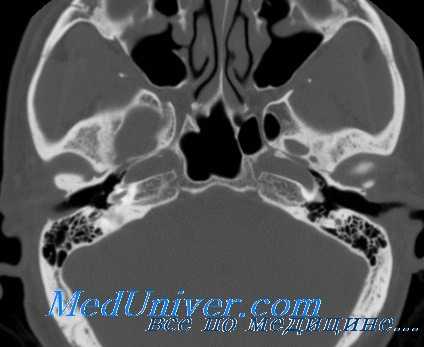

Отосклерозом называют патологический процесс, локализующийся преимущественно в лабиринтной стенке среднего уха около овального окна и заключающийся в лакунарном рассасывании компактной части стенки костного лабиринта и замещении ее спонгиозной пластинчатой костью. Этот процесс распространяется на кольцевидную связку окна преддверья и подножную пластинку стремени, в результате чего стремя замуровывается. Классическая форма отосклероза характеризуется ограничением подвижности стремени, в некоторых же случаях отмечается и полная его неподвижность (ankylosis stapedis).

Отосклероз не сопровождается развитием воспалительного процесса в среднем ухе; gневматизация сосцевидного отростка полностью сохраняется.

Происходящие при отосклерозе изменения костной ткани капсулы лабиринта иногда определяются по результатам прицельной рентгенографии черепа. Однако более информативным исследованием является КТ черепа, позволяющая визуализировать очаги отосклероза.

КТ височных костей. С обеих сторон диффузное снижение пневматизации ячеек сосцевидного отростка и пирамиды височной кости за счет отосклероза